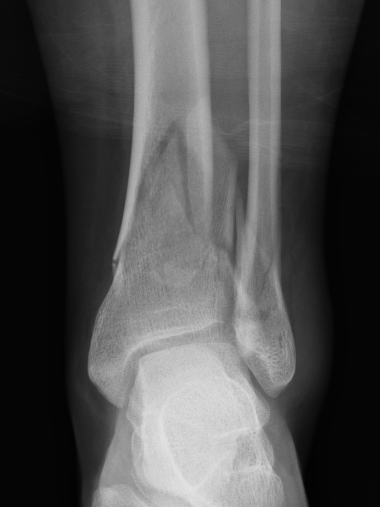

Intra-articular Extension

Posterior Malleolar Fractures

- occult in 70%

- especially with spiral distal tibial fractures

Posterior malleolar fixation

Typically stabilize intra-articular fracture first